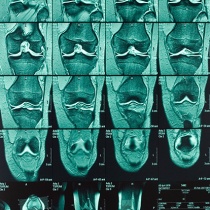

Les examens complémentaires de contrôle sont essentiellement ceux de l’imagerie médicale, qui permettent de suivre l’évolution de l’arthrose et éventuellement l’effet du traitement.